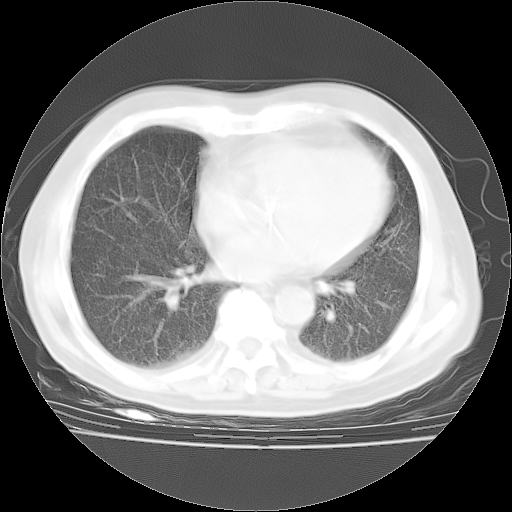

4月28日肺部CT——再次出现类似去年5月9日——磨玻璃样、间有“粟粒样”改变。